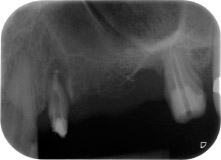

58-годишна пациентка се оплаква от болка и повишена подвижност в нейния мост върху зъб 24 с функция на абатмънт. На лице е периодонтално възпаление с дълбочина на джоба 7 mm мезиобукално и повече от 12 mm дистално, както и включена 3 градусова фуркация. Освен това, рентгенографията показва обширна периодонтална лезия около апикалната зона на (друго място) предварително ендодонтски обработен зъб 24 (Фиг. 1).

В букалния корен, цялата вестибуларна и дистална кост липсва. Захващането е значително ограничено до палатиналния корен, подчертавайки предварително лошата прогноза. Зъб 27 също откри намалено хоризонтално захващане и минимално апикално разреждане (Фиг. 1) без клинични симптоми.